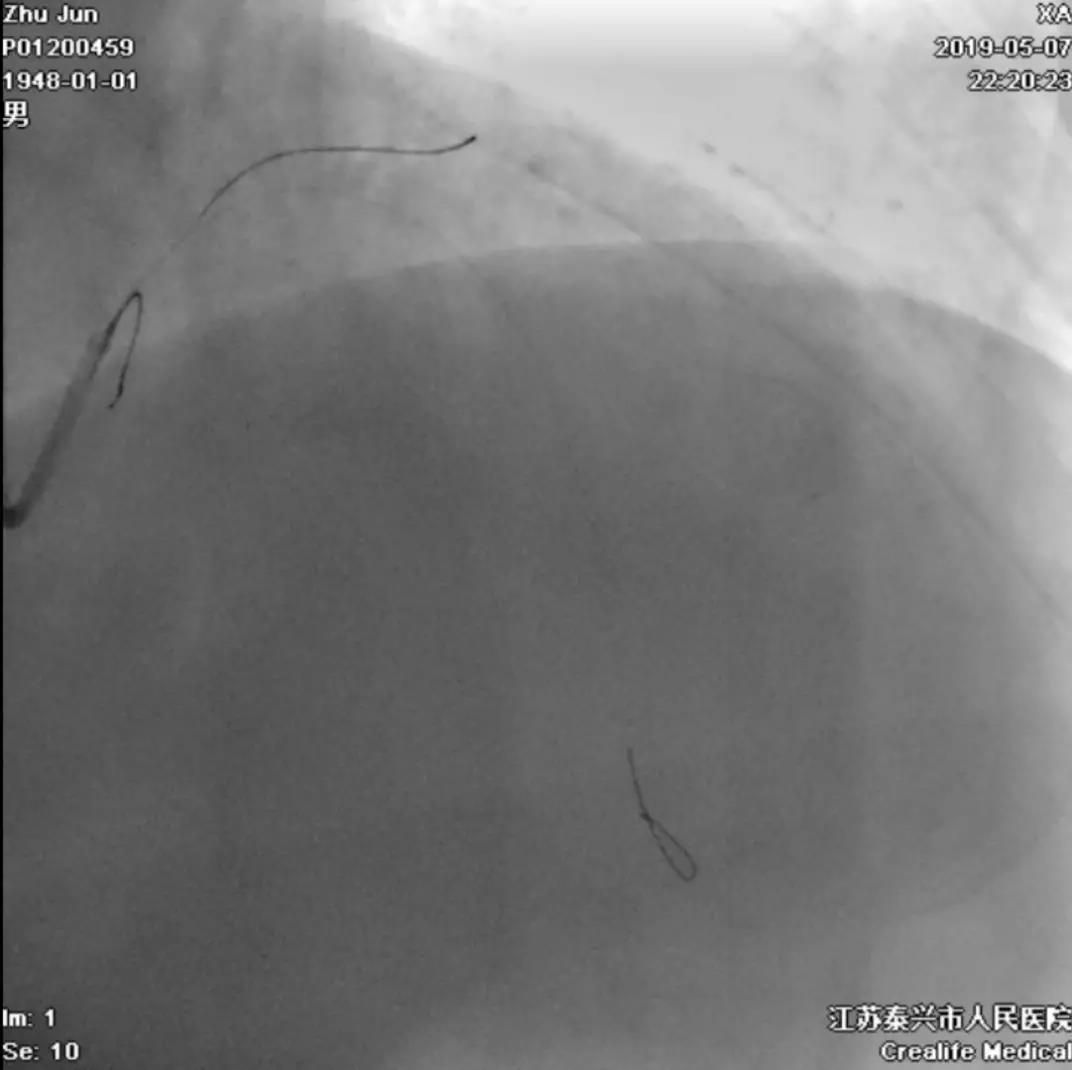

手术即刻效果完美,患者存活

术后即刻心电图

抬高的ST段基本回落

评价心肌再灌注治疗的效果,除了症状好转,还有心电图,就是一个直接而又简单的方法。胸前导联抬高的ST段(参见前面的术前心电图)在血管开通后的即刻就明显地回落,几乎回到了等电位线的水平,说明心肌的再灌注治疗非常成功。